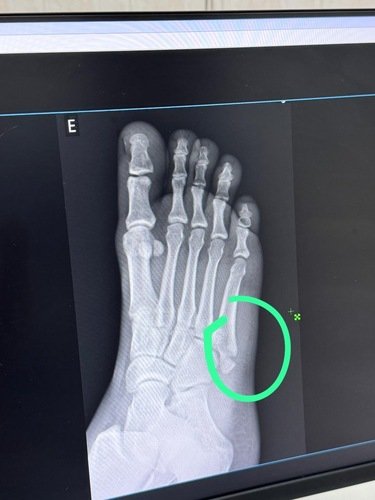

Sou Max Lima, um triatleta de 24 anos e educador físico. Sofri uma grave lesão ao descer as escadas de casa, fraturando o quinto metatarso do pé esquerdo. Para que eu possa continuar minha carreira como atleta, é essencial que eu passe por uma cirurgia urgente antes que ocorra a calcificação do osso. A cirurgia precisa ser realizada até o dia 20/09/2024 e custa R$15.000,00.

A fratura do quinto metatarso é uma lesão séria, especialmente para atletas. Este osso, localizado na parte externa do pé, é crucial para a estabilidade e a mobilidade. Em triatletas, que dependem intensamente dos pés para correr, pedalar e nadar, uma fratura como essa pode ser devastadora. Sem a cirurgia adequada, Max corre o risco de não conseguir retornar às competições, comprometendo sua carreira e seu sonho.